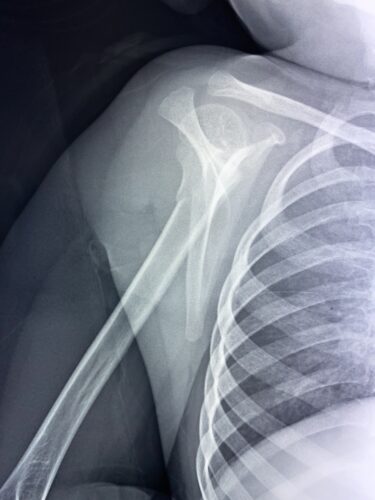

第11回整骨研究会「賜恩」研修会開催

さわやか千葉県民プラザ(上腕骨外科頸骨折)